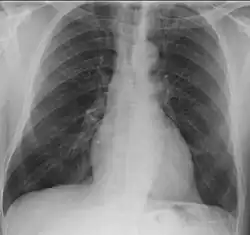

The left apical region is opacified in a case of granulomatosis with polyangiitis.

• Lungs: Abnormal chest X-ray with nodules, infiltrates, or cavities